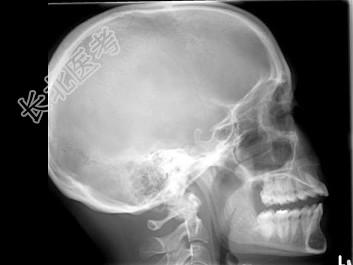

- 多项选择题女,25岁, 车祸伤及面部,X线及CT检查如图所示, 正确的描述或诊断是 ( )

A、X线示左侧眶底较正常变低

B、CT发现左侧眶底骨质断裂

C、左侧上颌窦内见气-液面

D、左侧眶底骨折

E、左侧上颌窦积液